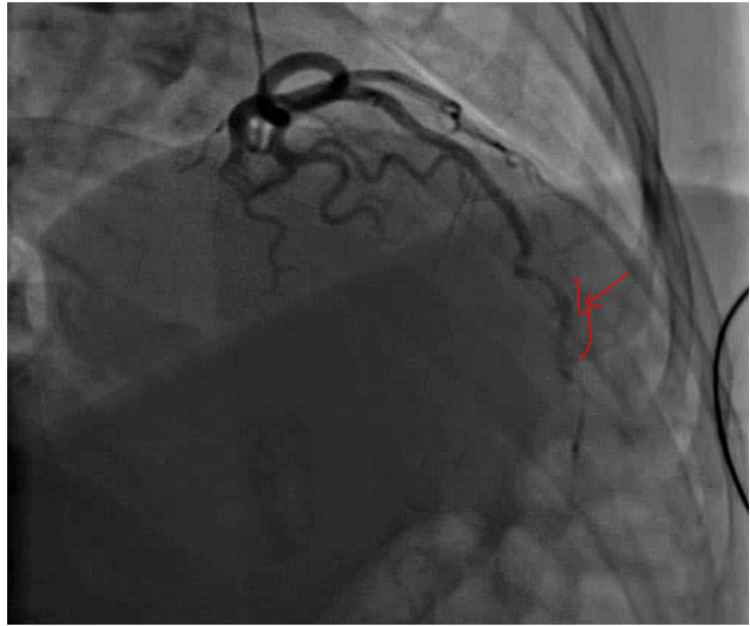

Her vital signs and physical examination were unremarkable; laboratory findings were significant for troponin I of 0.10 ng/ml x1 (peaked to 1.36 ng/ml x2), and urine toxicology was positive for THC. Her ECG, CXR, and TTE were normal and coronary angiography showed evidence of mid-distal LAD SCAD with TIMI grade II flow, as seen in Figure 2.